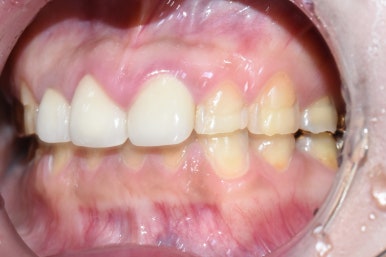

전 후 사진

지금까지 시청역 연세예감치과에서 알아본

부식된 노란 치아를 새하얗게 하고 싶은 환자분의

크라운(기존 크라운 제거하고 다시 크라운)과 라미네이트 케이스

-총 16개-였습니다.